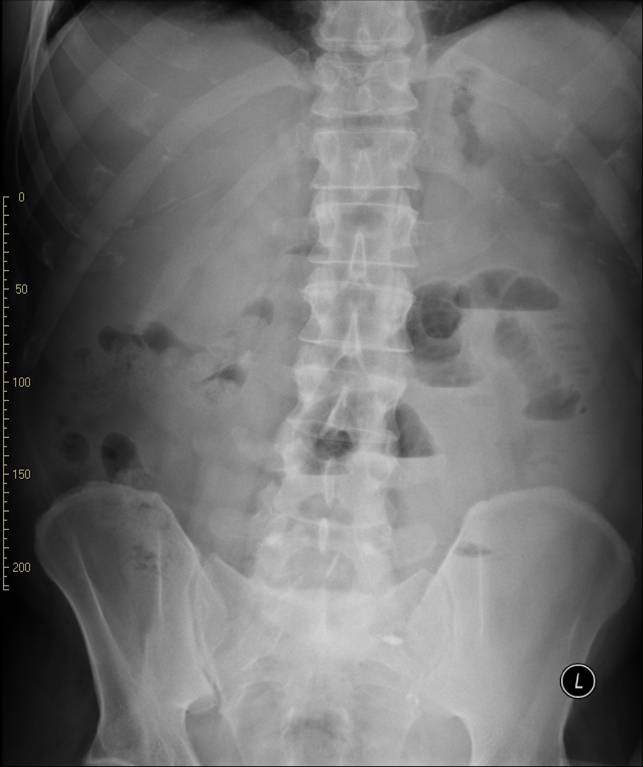

• The diagnosis of acute pancreatitis has to be based on the complex assessment of the patient. The results of all three: clinical picture, blood results (amylase value, inflammatory parameters) and imaging finding have to be considered. The positivity of at least two examinations can confirm pancreatitis. The role of diagnostic imaging therefore, is to differentiate other processes involving the periumbilical region or to assess the complications of pancreatitis. Peritoneal irritation caused by pancreatitis can create small bowel paralysis and air-fluid levels.

19. Plain abdominal X-ray, sentinel loop.

This paralytic, periumbilical bowel loop is also called sentinel-loop. If present, it can lead to the disruption of the ultrasound examination. Any gas filled intestine over the pancreatic region will cause the hyperreflection of the sound waves, thus leaving the middle portion of the retroperitoneum obscured to sonography. If the pancreatic region is still visible with ultrasonography, the pancreas appears widened; its structure shows edematous infiltration. Free fluid is usually detectable in the peripancreatic region, the omental bursa or in other cases there is a diffuse appearance of free fluid in the whole abdomen. CT examination can identify the early phase of acute pancreatitis. In the early, edematous phase the pancreas is widened and the peripancreatic fat appears hyperdense due to the edematous infiltration. Still, the main role of CT scanning remains the assessment of the early and late complications of pancreatitis. Edema, hemorrhage and necrosis each show typical features with CT, which help in the differential diagnostics.